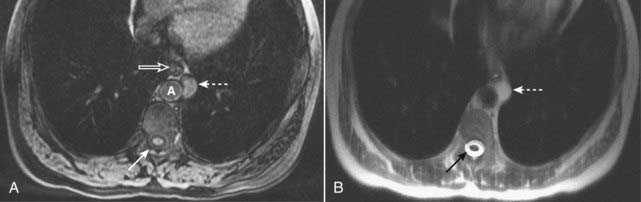

Figure 20-2 Subcapsular hematoma of the kidney.

A, Axial T1-weighted fat-suppressed image demonstrates a bright subcapsular hematoma (solid white arrows) involving the left kidney laterally. We can tell that this is a T1-weighted image because cerebrospinal fluid (CSF) in the spinal canal is dark (open white arrow). B, Axial T2-weighted, fat-suppressed image again demonstrates a slightly bright left subcapsular hematoma with a dark rim of hemosiderin (dotted white arrows) indicating surrounding older blood. There is a small amount of adjacent left perinephric fluid (solid white arrow). The bright signal of the CSF helps us to recognize this image as a T2-weighted image (open white arrow).

Figure 20-3 Proteinaceous enteric cyst.

A, Axial T1-weighted fat-suppressed image demonstrates a left-sided, mediastinal bright mass (dotted white arrow) adjacent to the esophagus (open white arrow) and aorta (A). Notice that this mass is brighter than the CSF in the spinal canal (solid white arrow). B, Axial T2-weighted image shows that the mass is T2 bright (dotted white arrow), but not as bright as the CSF in the spinal canal (solid black arrow). Contrast-enhanced images (not shown) demonstrated no enhancement. At surgery, this mass was found to represent a benign enteric cyst containing proteinaceous (as opposed to purely simple) fluid.